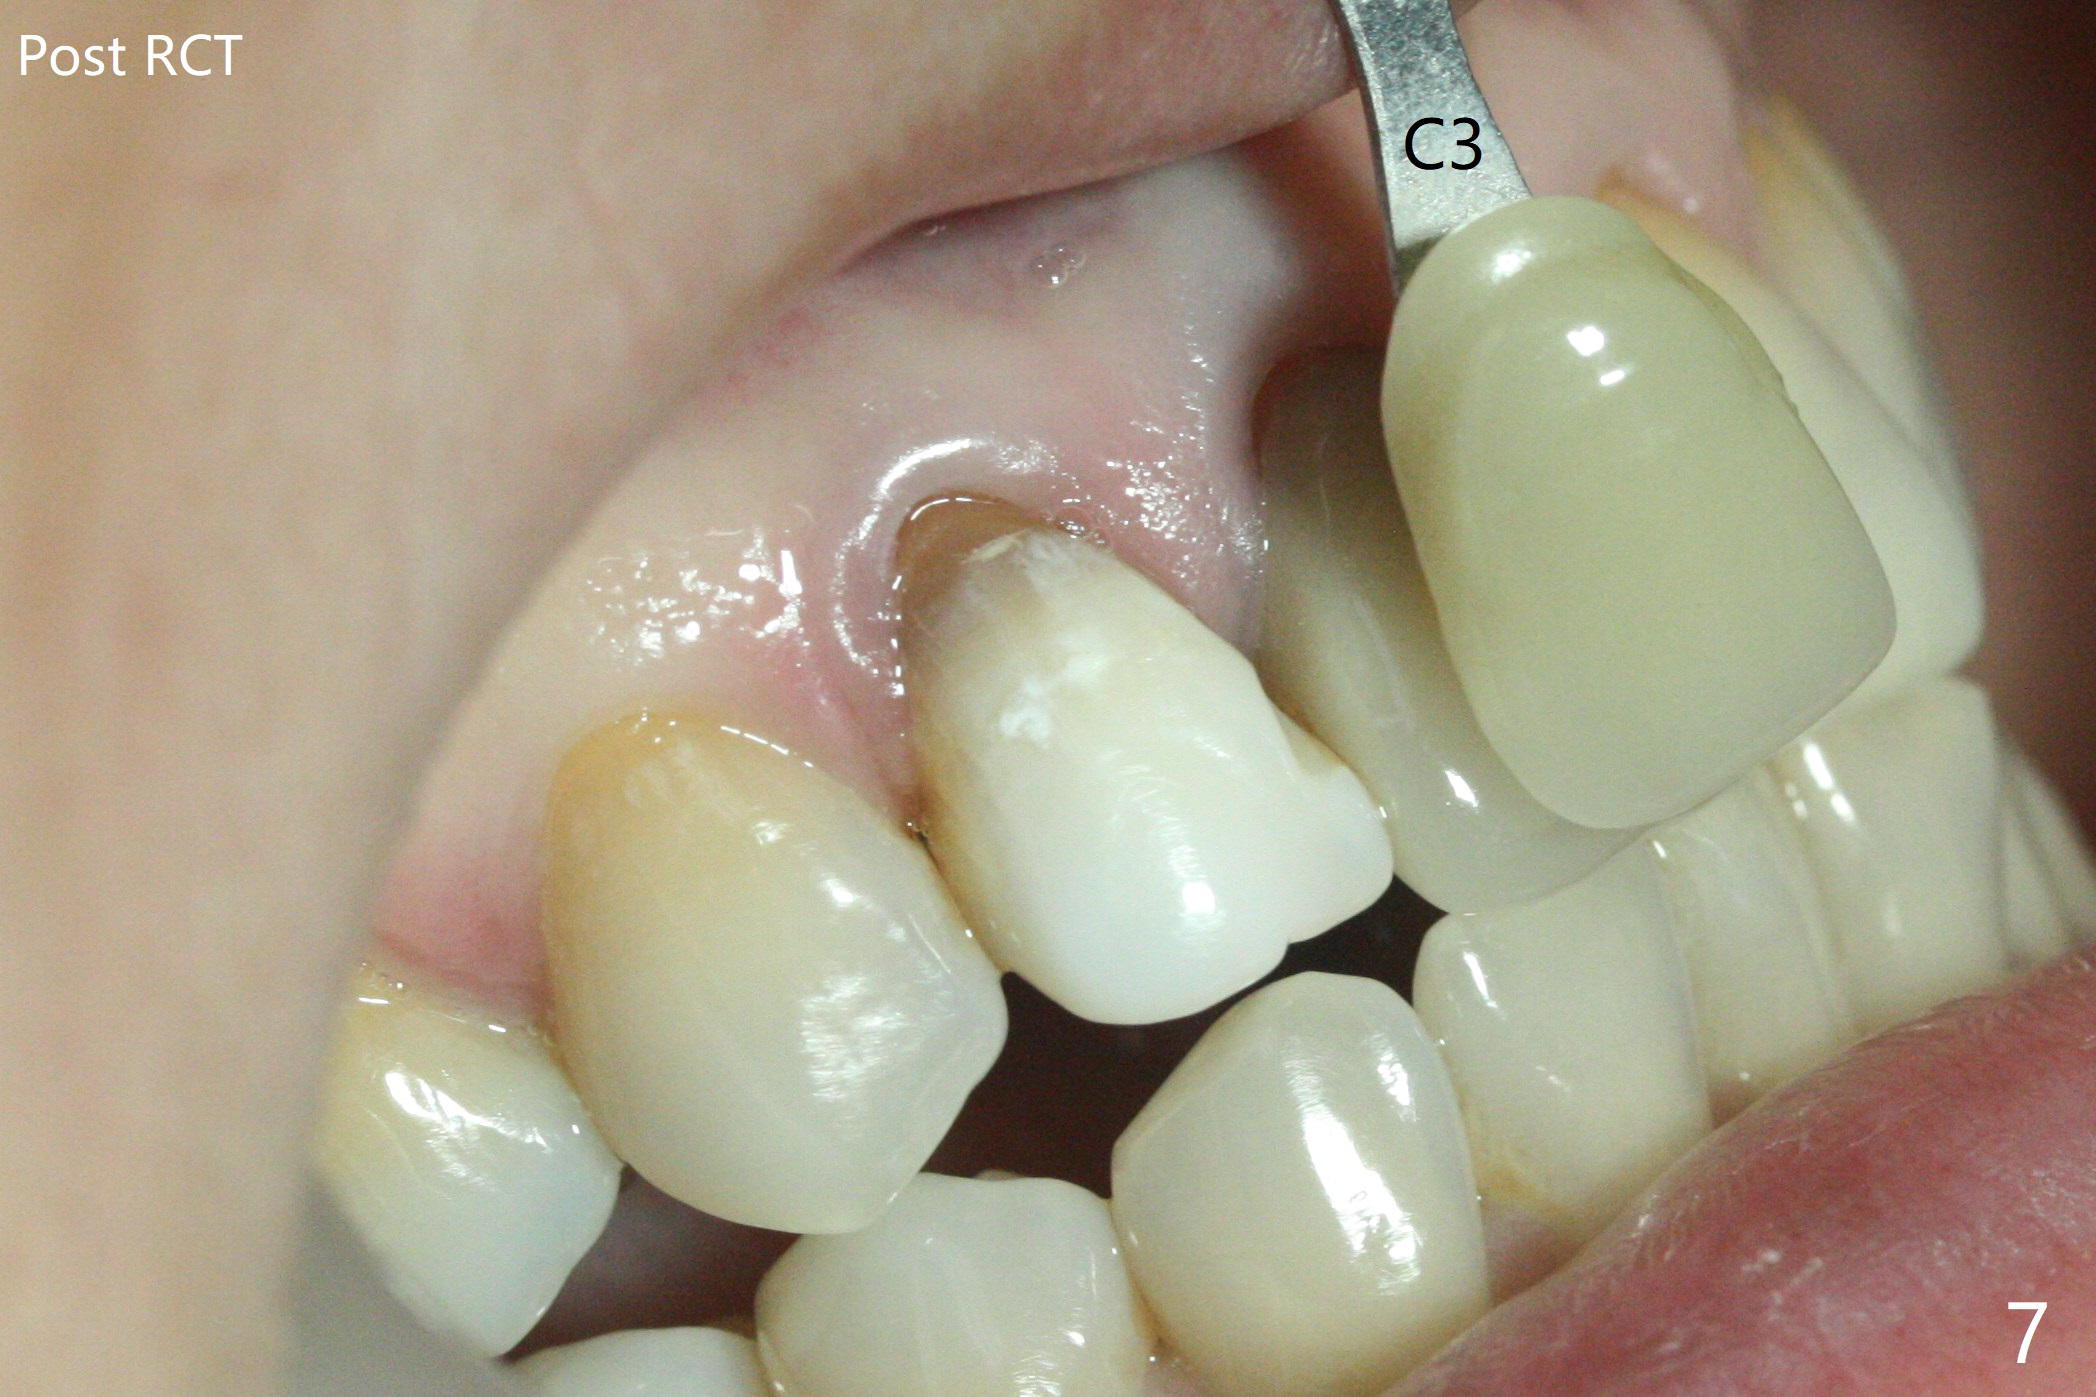

A 46-year-old woman requests a crown for the discolored tooth #7 (Fig.1,2) with mesiolingual composite (Fig.3 C) and periapical radiolucency (*). After RCT (Fig.4,5) with sodium hypochlorite, the tooth #7 is whiter than the ML composite (Fig.6,7). The patient returns 1 day post RCT for in house internal and external bleaching (Fig.8) with 35% hydrogen peroxide gel closed in the canal when she leaves. Three weeks later, the lateral incisor has the shade as the neighboring natural teeth (Fig.9,10). After the lightest shade composite placed in the canal and the access hole (Fig.11), the lateral looks better than the central with a crown and cervical discoloration (Fig.12).